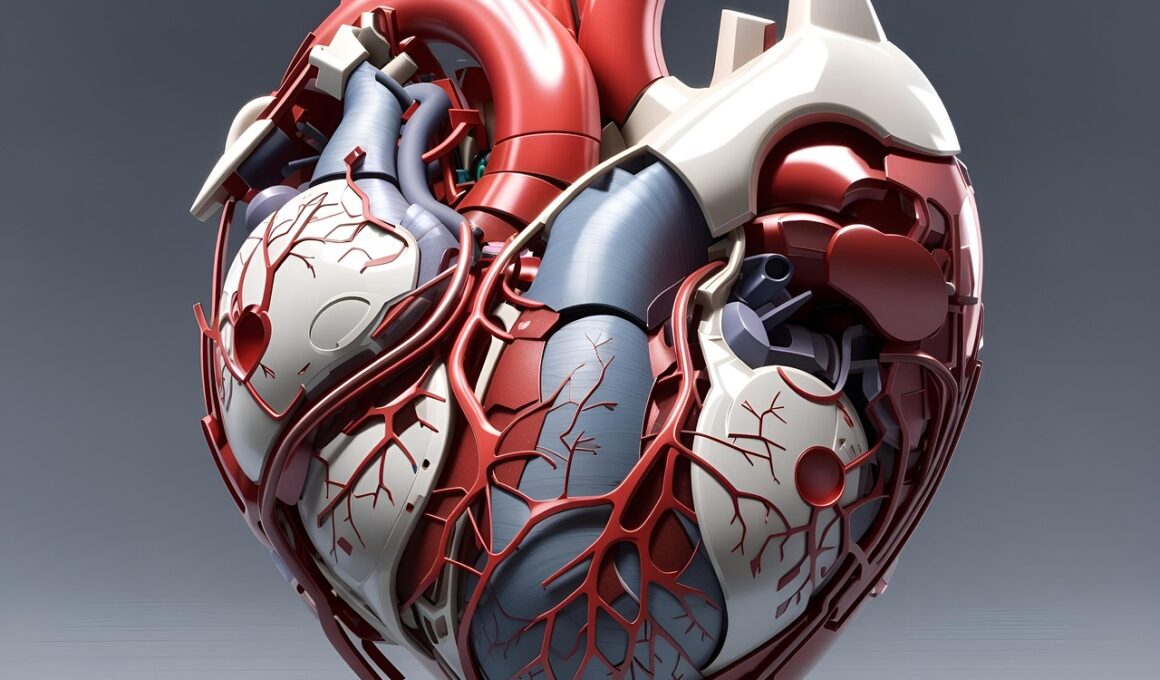

Smoking significantly affects men’s cardiovascular fitness, leading to decreased aerobic capacity and overall endurance. Studies reveal that men who smoke can expect a considerable reduction in lung function, which is essential for physical activities. The inhalation of harmful substances constricts blood vessels, increasing the risk of hypertension and heart disease. Moreover, smoking contributes to the accumulation of plaque in arteries, limiting blood flow and oxygen supply to vital organs. Consequently, men who smoke may find themselves fatigued during moderate exercises, reducing their ability to engage in cardiovascular routines. In contrast, quitting smoking can lead to improved cardiovascular health over time. Many fitness programs emphasize not only physical activity but also smoking cessation, promoting healthier lifestyles. Therefore, it’s crucial for men to consider the long-term impact of smoking on fitness levels. Exploring resources that aid in quitting smoking can be beneficial, fostering not just a healthier heart but also improved athletic performance. Eating a balanced diet and integrating cardiovascular exercises can further aid recovery from smoking’s detrimental effects, encouraging men to prioritize overall health in conjunction with fitness goals.

Regular exercise is pivotal in combating the negative effects of smoking and alcohol on cardiovascular fitness among men. Engaging in consistent aerobic activities such as running, cycling, or swimming can significantly enhance heart health. These forms of exercise improve circulation, strengthen heart muscles, and increase cardiovascular endurance. For men who are just beginning their fitness journey, starting with moderate exercises can reduce the likelihood of injury and promote gradual improvements. Over time, increasing the intensity and duration of workouts can lead to remarkable health benefits. Integrating interval training into routines challenges the cardiovascular system, resulting in enhanced fitness performance. Ensuring diverse exercises keeps routines fresh and exciting, reinforcing commitments to fitness. Furthermore, incorporating strength training can complement cardiovascular routines, boosting metabolism and aiding in weight management. Additionally, setting achievable fitness goals fosters motivation, facilitating a more structured approach to training. Assessing progress regularly also cultivates a sense of accomplishment, further driving dedication. Ultimately, a consistent exercise routine, combined with mindful practices regarding alcohol and smoking, empowers men to reach their fitness aspirations.

Understanding the effects of smoking and alcohol on recovery time is crucial for men focused on cardiovascular fitness. Injured or fatigued muscles require adequate time and resources to heal and grow stronger. Smoking slows blood flow, essential for muscle recovery, while alcohol can impair protein synthesis. Consequently, men who engage in cardiovascular activities while either smoking or consuming alcohol may experience prolonged recovery periods. This delay in recovery can hinder progress, leading to frustration and decreased motivation for regular workouts. Men should prioritize recovery strategies post-exercise, incorporating techniques such as stretching, hydration, and healthy nutrition. Incorporating rest days into fitness schedules is equally as essential, allowing muscles ample time to recuperate. Availability of resources such as physiotherapy or alternative treatments can also support recovery during demanding training phases. Furthermore, tracking recovery times through journals or apps may help men understand their bodies better. Through mindful practices focusing on recovery, men can enhance their cardiovascular fitness in a sustainable manner. Ultimately, recognizing and addressing these factors fosters resilience, enabling continuous engagement in fitness activities over time.